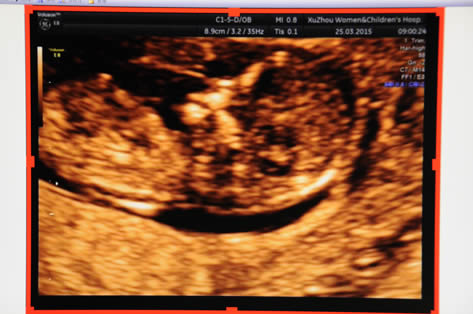

NT超聲成像

產科:早孕(yùn)期NT、普通產科、係統(tǒng)超聲(四維)、針對性產前超聲、單項產科等;